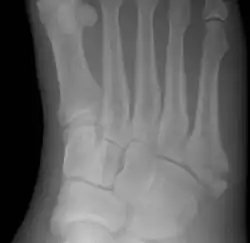

![]() | |

| Jones fracture as seen on Xray | |

A Jones fracture is a broken bone in a specific part of the fifth metatarsal of the foot between the base and middle part[8] that is known for its high rate of delayed healing or nonunion.[4] It results in pain near the midportion of the foot on the outside.[2] There may also be bruising and difficulty walking.[3] Onset is generally sudden.[4]

The fracture typically occurs when the toes are pointed and the foot bends inwards.[6][2] This movement may occur when changing direction while the heel is off the ground such in dancing, tennis, or basketball.[9][10] Diagnosis is generally suspected based on symptoms and confirmed with X-rays.[3]

Diagnostic X-rays include anteroposterior, oblique, and lateral views and should be made with the foot in full flexion.